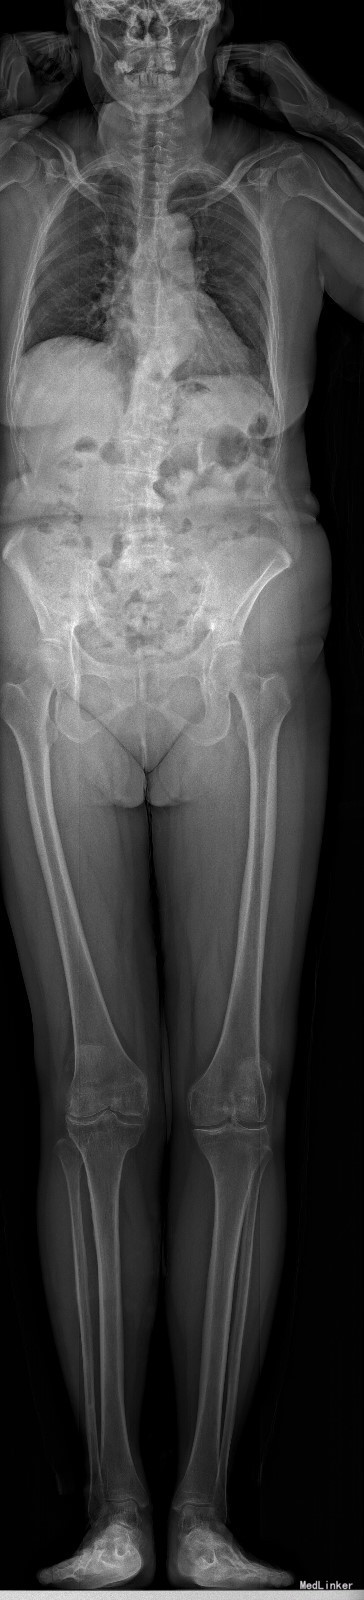

查体:脊柱无明显侧弯,腰背部无压痛,双下肢麻木酸痛,可牵连至脚跟。肌力肌张力可。腰部活动可,前屈后伸时感酸痛,无力。左侧直腿抬高试验阳性。 辅助检查:X线平片:腰椎侧弯前屈,L3椎体轻度滑脱,各椎间隙狭窄,腰椎退行性改变。 MRI:L4-5,L5-S1椎间盘膨出,L2-3,L3-4,L5-S1椎间隙狭窄,S2-3水平骶管内蛛网膜囊肿,腰椎序列不稳定,生理曲度局部后凸。

诊断:1 脊柱侧弯 伴不稳 2椎管狭窄 治疗: 前期微创腰椎侧路融合手术+后期 微创后路经皮内固定